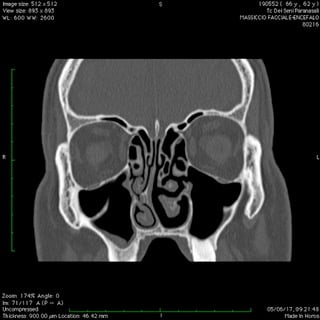

Anche nelle sinusiti la peculiare morfologia anatomica delle strutture coinvolte, cavità ossee, consente nella maggior parte dei casi latenze di esordio molto ritardate rispetto il primitivo insorgere patologico palesandosi così in avanzate fasi di compromissione .

Nelle forme croniche, cioè di malattia stabile nel tempo, i seni paranasali diventano “ siti di decantazione”, ovvero di ristagno e moltiplicazione,per germi di vario genere dando vita così ad un persistente primario serbatoio contaminante sia le vie aeree che quelle digestive.